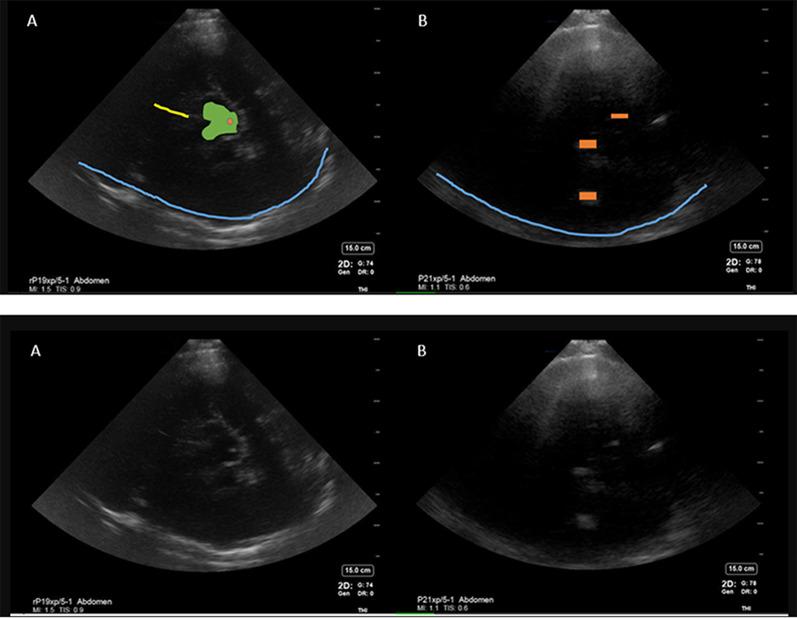

After obtaining IRB approval, a blinded investigator performed cranial ultrasound (Fujifilm, Sonosite Xporte, transcranial and abdominal presets) through temporal windows on 11 patients with intracerebral pathology within 72 h of last CT/MRI (computed tomography scan/magnetic resonance imaging) brain after being admitted to a neurocritical care unit in Aug 2020 and Nov 2020-Mar 2021. Images were then compared to patient's CT/MRI to inform topography. Inferential statistics were reported.

Mean age was 57 (28-77 years) and 6/11 were female. Six patients were diagnosed with ICH, 3 with ischemic stroke, 1 subarachnoid hemorrhage, and 1 brain tumor. The sensitivity and specificity of point of care diagnosis of ICH compared to CT/MRI brain was 100% and 50%, respectively. Mean time between ultrasound scan and CT/MRI was 13.3 h (21 min-39 h). Falx cerebri, choroid calcification and midbrain-related artifacts were the most reproducible hyperechoic signals. Abdominal preset on high gain yielded less artifact than Transcranial Doppler preset for cranial B mode imaging. False positive ICH diagnosis was attributed to intracerebral tumor and midbrain-related artifact.

平均年龄为57岁(28 - 77岁),11例中有6例为女性。6例患者被诊断为ICH,3例为缺血性卒中,1例为蛛网膜下腔出血,1例为脑肿瘤。与头颅CT/MRI相比,POCUS诊断ICH的敏感性和特异性分别为100%和50%。超声扫描与CT/MRI之间的平均时间为13.3小时(21分钟 - 39小时)。大脑镰、脉络丛钙化和中脑相关伪像是最可重复的高回声信号。对于头颅B模式成像,腹部预设在高增益时产生的伪像比经颅多普勒预设少。ICH诊断的假阳性归因于脑肿瘤和中脑相关伪像。